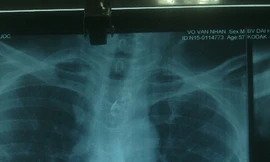

TPO - Ngày 16/10, bác sĩ Lê Quang Nhân - Trưởng khoa nội soi Bệnh viện Đại học Y Dược TPHCM - cho biết, bệnh nhân V.V. N. (57 tuổi, ngụ Bến Tre) nhập viện cấp cứu trong tình trạng đau dọc sau xương ức sau khi nuốt phải xương cá ngát 3 ngày trước đó.